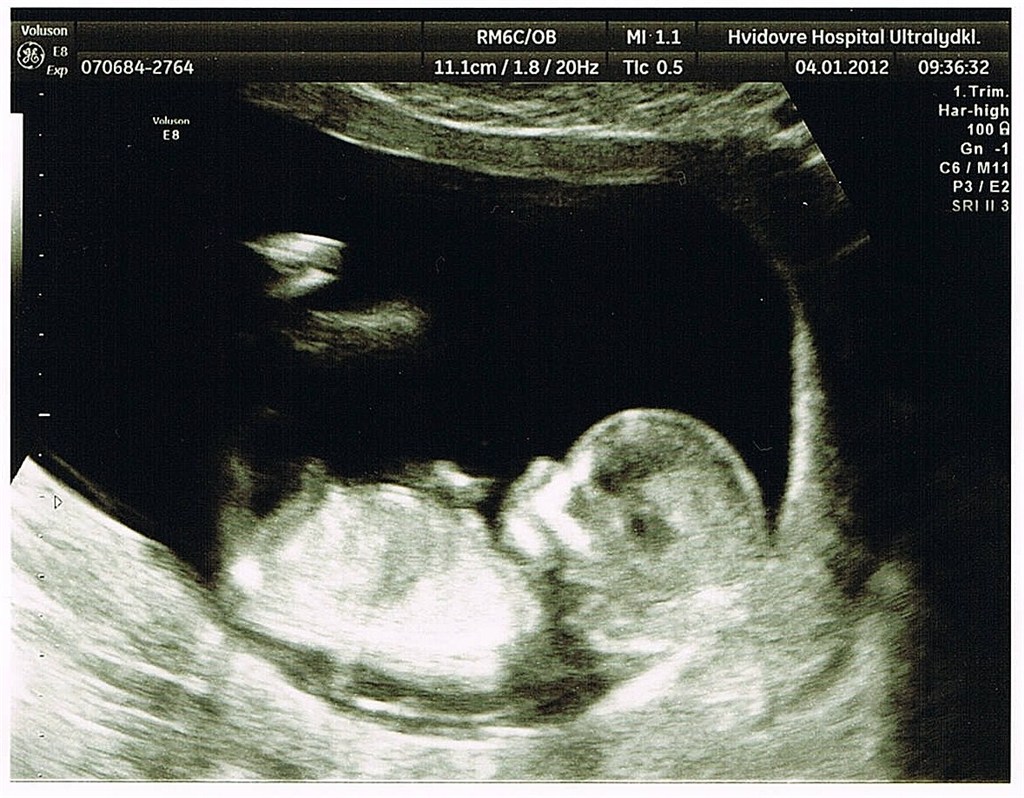

fine tal på 1:2990 på begge tvillinger og jeg blev rykket frem til at være 13+4

De fastatte nu endelig til at være enæggede tvillinger med hver deres foterhinde men samme moderkage. Dette skræmmer mig lid da det betyder scanninger hver 14 dag indtil termin og en masse undersøgelser.....